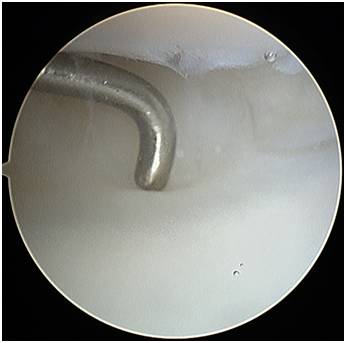

Radio-carpal arthroscopy was done with the 3-4 (between the 3rd and 4th dorsal extensor compartments) portal as the viewing portal and the 4-5 (between the 4th and 5th dorsal extensor compartment) portal as the working portal. The joint was very difficult to scope due to the findings of a “snowstorm” of fibrotic plica bands (Figure 1), thickened synovium covering the TFCC (Figure 2) and further synovitis in the ulno-carpal recess (Figure 3). After debriding all these layers of tissues, the TFCC was found to be intact but stretched over the congenitally deformed ulnar head (Figure 4). There was also early stage chondromalacia of the lunate fossa of the radius.

Figure 1 Left wrist radio-carpal arthroscopy (lunate on top, radius at the bottom) demonstrating the “snowstorm” of thick fibrous plica bands assessed with a probe (seen in the centre).